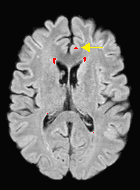

Patch size is another important parameter of the network. In computer vision applications such as object detection, usually a whole 2D image is used as a feature. However, full 3D medical images can not typically be used because of memory limitations. Fig. 4 shows examples of lesion memberships obtained with different sized 2D patches. As the patch sizes increases, the false positives that are mostly observed in the cortex tend to decrease. Fig. 5 shows a plot of Dice and LFPR with various patch sizes, ordered from left to right according to their increasing size. Note that smaller patches ( to ) produced significantly lower Dice and higher LFPR compared to other patches (), as seen from the memberships in Fig. 4. Also some of the highest Dice and lowest LFPR were observed for patches with large in-plane size, i.e., , , and . It was observed in Fig. 5 that there is no significant difference between Dice coefficients for , , or , but LFPR of both and are significantly lower than that of (). We chose as the optimal patch size. Other choices of smaller and patches (not shown) yielded worse results. Note that although training was performed with different patch sizes, the memberships were generated slice by slice, as the trained model consisted only of convolutions and did not need any information about patch sizes.